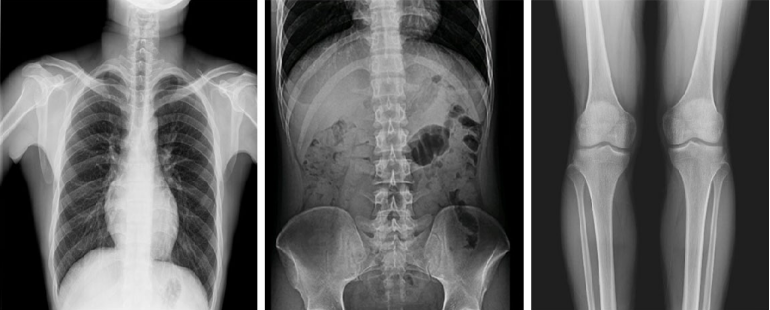

而且,影像采集幅面大,17×17英寸超大視野可覆蓋成年人的全胸全腹,并且能在連續(xù)動態(tài)中實(shí)時高清點(diǎn)片,從而達(dá)到精準(zhǔn)診斷的目的。設(shè)備靈活高效的多維度運(yùn)動設(shè)計(jì),也帶來了更加智能化、人性化操作體驗(yàn),可大幅提升檢查效率。

與此同時,普利德動態(tài)平板DRF還具有全身拼接功能,尤其適用于全脊柱和全下肢攝影,為臨床提供高精度圖像,輔助脊柱畸形矯形治療、康復(fù)檢查。